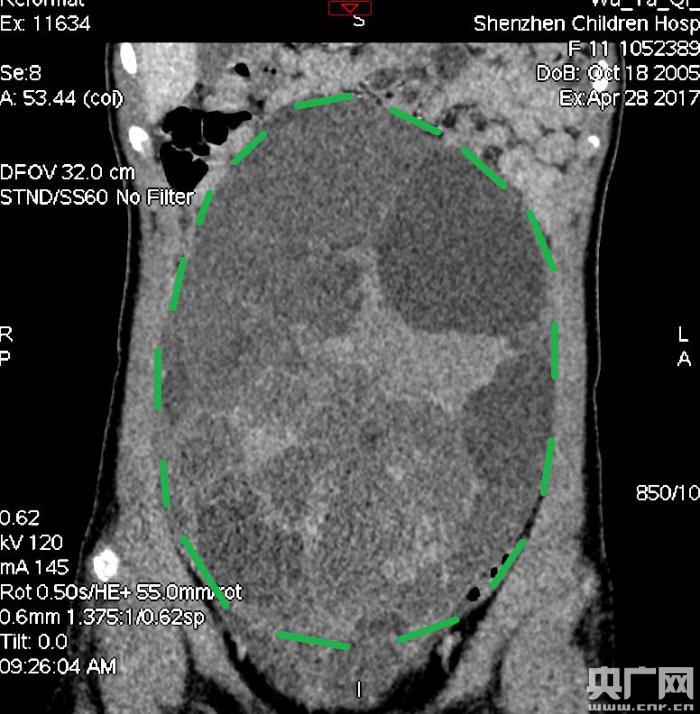

入院后,普外一科肖東主任向家長詢問了病史,仔細(xì)進(jìn)行了體格檢查,并完善腹部CT。CT結(jié)果提示,孩子的大部分腹腔、盆腔被一個(gè)巨大的腫瘤占據(jù),腸道、血管和腎盂都受到了不同程度的壓迫。從CT上看,腫瘤很可能起源于左側(cè)的卵巢。

手術(shù)中發(fā)現(xiàn),小琪腹中的腫瘤體積巨大,大小約為25×20×15厘米,表面光滑,來源于左側(cè)卵巢。醫(yī)生們首先將其與周圍的組織小心剝離,然后將這個(gè)占據(jù)孩子腹腔、盆腔大部分的巨大包塊完整切除,切除腫瘤后還重建了左側(cè)卵巢。剖開瘤體,發(fā)現(xiàn)瘤體為囊性及實(shí)性混合組成,瘤體內(nèi)部充盈著粘液狀的液體,重量達(dá)到了3000克。術(shù)后小琪病情穩(wěn)定,測(cè)量腹圍從術(shù)前的72厘米減小到了62厘米。